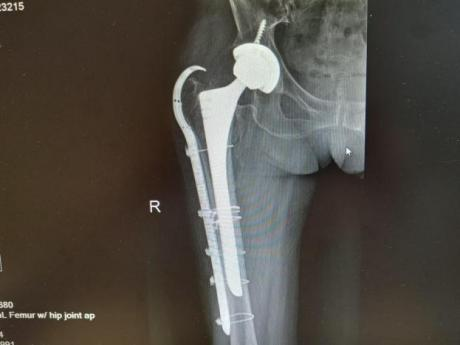

4月23日,贵州航天医院第58次晨读会由我院骨科副主任医师张艳金作学术交流,他以“加速康复指导下的快速手术”为题,详细讲解了老年股骨粗隆间骨折与儿童四肢骨折的临床诊疗难点,结合加速康复外科(ERAS)核心理念,重点阐述了ERAS理念在两大人群中的创新实践,实现患者入院后6至24小时内即可接受手术治疗。针对老年髋部骨折患者,提出通过多学科协作(MDT)与微创手术优化围术期管理,在确保安全前提下缩短术前等待时间,实施精准化麻醉及术后康复方案,可有效降低并发症发生率、改善患者生活质量和预后效果。在儿童骨折领域,强调微创术式与心理干预并行的双轨策略,既减少手术创伤对骨骼发育的影响,同时关注患儿心理疏导,实现生理功能与心理健康同步康复。并通过典型案例的影像学资料与随访数据,直观展示了ERAS理念指导下骨科治疗模式的创新成果。 贵州航天医院骨科 专家简介 赵学平 中共党员,骨科党支部书记、主任,主任医师 临床擅长:从事骨科临床工作30余年,对骨科常见疾病的诊治具有丰富的临床经验。 世界中医药联合会脊柱康复专业委员会常务理事,中华中医药学会整脊分会常务委员,中国中西医结合学会骨伤科分会肢体矫形功能重建与康复专家委员会常务委员,中国研究性医院学会骨科创新与转换专业委员会关节外科学组保髋工作委员会常委,中国康复技术转化及发展促进会骨外科与康复技术转化专业委员会常务委员,泛珠三角区域运动医学联盟(PPRD-SMA)理事会常务理事,中国研究型医院学会运动医学专业委员会委员,贵州省中医药学会整脊分会副主任委员,贵州省中西医结合学会银质针专业委员会副主任委员,贵州省康复医学会骨与关节专业委员会常务委员,贵州省人民医院骨科专科联盟常务理事,贵州省康复医学会骨内科专业委员会常务委员,中华医学会贵州省骨科学会委员,贵州省康复医学会脊柱脊髓专业委员会常务委员,贵州省运动医学分会委员,贵州省康复医学会骨与软组织肿瘤专业委员会委员,遵义市医学会创伤分会副主任委员,贵州省康复医学会骨内科专业委员会遵义地区分会常务委员,遵义市医疗事故鉴定、伤残鉴定、工伤鉴定、司法鉴定专家。 长期从事骨科临床研究及教学工作,在国家级、省部级杂志发表论文20余篇,SCI论文2篇,参与主编骨科专著2部,主持省部级科研项目2项,参与指导省部级、市级科研项目6项。 陈明勇 骨科副主任,副主任医师 临床擅长:从事创伤骨科工作约20年,对骨缺损、骨不连、骨肿瘤、肢体畸形等的肢体矫形重建及功能重建,慢性化脓性骨髓炎的根治治疗、糖尿病足的保肢治疗、快速康复理念(ERAS)下的老年骨折的诊治,四肢复杂骨折的诊治,四肢骨折等微创手术治疗具有丰富的临床经验。 2004年毕业于遵义医学院临床专业,曾在中国人民解放军总医院、广西医科大学第一附属医院、上海第六人民医院骨科进修。中国中西医结合学会骨伤科专业委员会横向骨搬移治疗糖尿病足及微血管网再生学组首届委员,遵义市医学会创伤分会常务委员。 瞿 辉 中共党员,骨科副主任医师 临床擅长:对骨科的常见病、关节外科、脊柱外科及运动医学疾病的诊治具有丰富的临床经验,熟练掌握骨科手术操作技术。 毕业于遵义医学院临床医学系,2005年前往广州中山大学第一附院骨显微医学部进修学习,2011年前往成都华西医院进修学习,并多次在省内外学习骨科相关知识,是中华医学会骨科分会会员。 赵兴东 骨科主任医师 临床擅长:擅长骨科的常见病及各种创伤、四肢骨折创伤修复、骨感染、手足疾病的诊治和手足体表畸形的矫形整复,熟练掌握骨科四肢骨病及创伤的手术操作技术,尤其在四肢关节复杂性损伤、手足外伤、组织缺损创面、难治创面的皮瓣修复方面及平足、高弓足矫形方面及四肢慢性疼痛诊治、康复方面具有丰富的临床经验。 硕士研究生,毕业于遵义医学院临床外科系,2015年前往山东省立医院手足外科进修学习;遵义市医学分会创伤分会第一、二届委员,遵义市手外科医学会第二委届员会常务委员;在省级及省级以上期刊发表文章9篇,参编著作2部,参与主持并完成市级课题1项,参与市级课题2项、省级课题1项。 张艳金 中共党员,骨科副主任医师 临床擅长:从事骨外科工作16年,对复合伤、多发伤的救治、四肢骨干骨折、关节周围骨折、骨肿瘤、骨髓炎等诊治具有丰富的临床经验。 中共党员,硕士研究生,2006年本科毕业于山西医科大学第二临床医学院,2011年研究生毕业于北京军区总医院;在“老年COPD患者合并髋部骨折的诊治”国际合作课题组研究两年,在老年髋部骨折的诊治方面具有丰富的经验,并发表论文6篇;主持遵义市级课题1项,承担遵义医科大学的临床教学工作,获得遵义医科大学优秀带教老师荣誉。编撰有《骨科疾病诊疗精粹》一书,开展2项新技术,编撰地方规范《务川自治县创伤骨科常见疾病诊疗规范》一书。 张俊凯 骨科副主任医师 临床擅长:从事骨科临床工作28年,对创伤骨折、骨感染、骨缺损、骨不连等外科诊治,四肢骨折的微创手术治疗,四肢复杂骨折(如关节内粉碎性骨折、多发骨折等)的损伤控制及手术治疗等具有丰富的临床经验。 1995年毕业于遵义医学院临床专业,2009年前往复旦大学附属医院骨科进修1年。 卢懿明 中共党员,骨科副主任医师 临床擅长:从事骨科工作18年,对创伤骨折、四肢骨折的微创手术治疗、四肢复杂骨折(如关节内粉碎性骨折、多发骨折等)的损伤控制及手术治疗,尤其是髋部骨折的PFNA等微创技术,踝关节骨折、膝关节周围骨折的Mipo微创技术等具有丰富的临床经验,开展了4项新技术,发明6项新型专利技术。 2005年毕业于遵义医学院临床专业,2017年,前往南方医科大学第三附属医院骨科进修半年,回院后运用Mipo技术对骨干骨折及干骺端骨折的治疗技术,同时积极开展骨盆骨折、髋臼骨折腹直肌外侧切口的应用;发表了多篇专业论文,经常参与省内外学术交流会授课,获得医院荣誉称号多个。 邬夏荣 骨科副主任医师 临床擅长:从事骨科工作16年,对四肢复杂骨折、骨肿瘤的诊治,尤其是足踝创伤、慢性踝关节损伤、平足症等诊疗具有丰富的临床经验。 2006年毕业于遵义医科大学临床医学专业,曾在陆军军医大学西南医院进修学习,发表多篇骨科学术论文。 余德怀 中共党员,骨科副主任医师 临床擅长:从事骨科工作10余年,对运动医学、骨关节、脊柱外科常见病、多发病的诊治具有丰富的临床经验。 硕士研究生,2011年毕业于遵义医学院临床医学专业,曾前往遵义医科大学附属医院运动医学专业进修学习;是贵州省医学会运动医学分会青年委员,西部关节镜联盟委员;发表多篇骨科学术论文。 冯 乾 骨科副主任医师 临床擅长:从事骨科工作近20年,熟练掌握骨科多发病及常见病的诊治,尤其对脊柱退变性疾病的诊断及治疗具有丰富的临床经验,主要研究脊柱微创相关治疗方式,能熟练开展椎间孔镜及UBE。 曾前往北京大学第三医院进修学习疼痛及椎间孔镜、首都医科大学友谊医院专业进修脊柱内镜;是贵州省康复医学会第三届脊柱脊髓专业委员会委员;发明专利3项、发表脊柱外科专业论文多篇。 赵小锋 中共党员,骨科副主任医师 临床擅长:从事骨科临床工作11年,对骨科常见病、多发病诊疗有较为丰富的临床经验,擅长脊柱相关疾病诊断及治疗,尤其是颈、腰、腿疼痛疾病诊断及治疗,擅长胸腰椎骨折微创经皮穿刺内固定术、经皮穿刺椎体成形术、经皮穿刺脊柱内镜下腰椎间盘摘除术、单纯开创腰椎间盘摘除术、腰椎滑脱复位椎间植骨椎融合内固定术、腰椎管狭窄减压融合内固定术及人工髋、膝关节置换术等。 2012年毕业于遵义医学院外科学专业硕士研究生,2019年参加“遵义市115医学人才精英计划”于上海交通大学第一附属医院培训学习,2023年于北京大学第三人民医院脊柱外科进修学习,曾获得遵义市优秀医师荣誉称号。 遵义市手外科第一届委员,遵义市医学会创伤分会第一届委员,遵义市医学会创伤分会第二届委员,贵州省康复医学会第三届脊柱脊髓专业会委员,遵义市医学会烧伤与整形外科学分会委员,发表论文5篇,其中国家级核心期刊1篇,SCI论文1篇,主持市级课题1项并结题,参与市级课题2项。 贵州航天医院骨科 简介 基本情况 贵州航天医院骨科组建于20世纪60年代,前身是以创伤和断肢(断指)再植闻名于世的上海市第六人民医院骨科,中国断肢(断指)再植的奠基者、中科院院士陈仲伟等著名专家、学者多次莅临科室指导医疗、教学,是贵州省最早拥有专业骨科技术科室之一,在70年代开展了贵州省首例断肢(断指)再植手术。组建50余年来,诊治患者已逾百万,挽救了无数的伤病员,成为了保障遵义地区人民群众健康的重要支撑。 经过几代人的不懈努力,今天的骨科,已由创伤骨科发展至骨病、骨肿瘤、骨结核等领域,现有脊柱外科、关节外科、四肢创伤、手足外科四个亚专科,成为了集医疗、教学、科研于一体的综合学科,是贵州省临床重点专科、遵义市临床重点专科、遵义市骨科临床医学中心、遵义市基层骨科专科联盟理事长单位。 科室目前开放床位110张,共有医护人员50余人,副高级以上专家18人,硕士研究生15人。拥有一流骨科医疗设备多台,每年不定期选派优秀技术骨干到全国各大知名医学院校进修、学习、参观、交流,并邀请国内、国外知名专家教授来院进行交流、指导,通过不断引进国内外先进的诊疗技术,科室医疗技术水平稳步提升,为广大人民群众提供了优质的医疗服务。 专科特色 骨一科 (一)骨缺损、骨不连的肢体与功能重建 胫骨横向骨搬移技术治疗糖尿病足: (二)慢性骨髓炎的根治治疗 (三)肢体缺血性疾病如糖尿病足、脉管炎的保肢治疗 (四)皮瓣修复 (五)复杂创伤的治疗 (六)老年髋部骨折及小儿骨折快速手术 老年髋部骨折: 骨二科 (一)胸腰椎骨折微创经皮椎弓根螺钉固定术 (二)老年性骨质疏松性患者腰椎滑脱脊柱内固定术(骨水泥螺钉) (三)V形双通道脊柱内镜技术(VBE)腰椎融合术治疗腰椎退行性疾病 (四)老年性骨质疏松性骨折(PVP/PKP)术 (五)人工髋关节置换术 (六)双侧股骨头坏死人工全髋关节置换 (七)右侧全髋置换术后假体周围骨折翻修 (八)人工膝关节置换术 (九)人工膝关节假体松动翻修 (十)关节镜技术 传统手术切口 关节镜技术切口 诊疗范围 骨一科 1.四肢创伤、矫形。 2.手、足踝外科。 骨二科 end